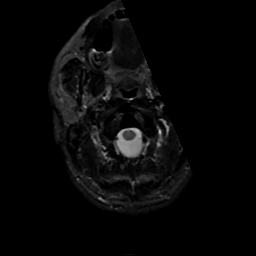

MR Study #7, March 24, 1991 -- Slice #0

[Home][Help][Clinical][Tour 1][Tour 2] Slice 0